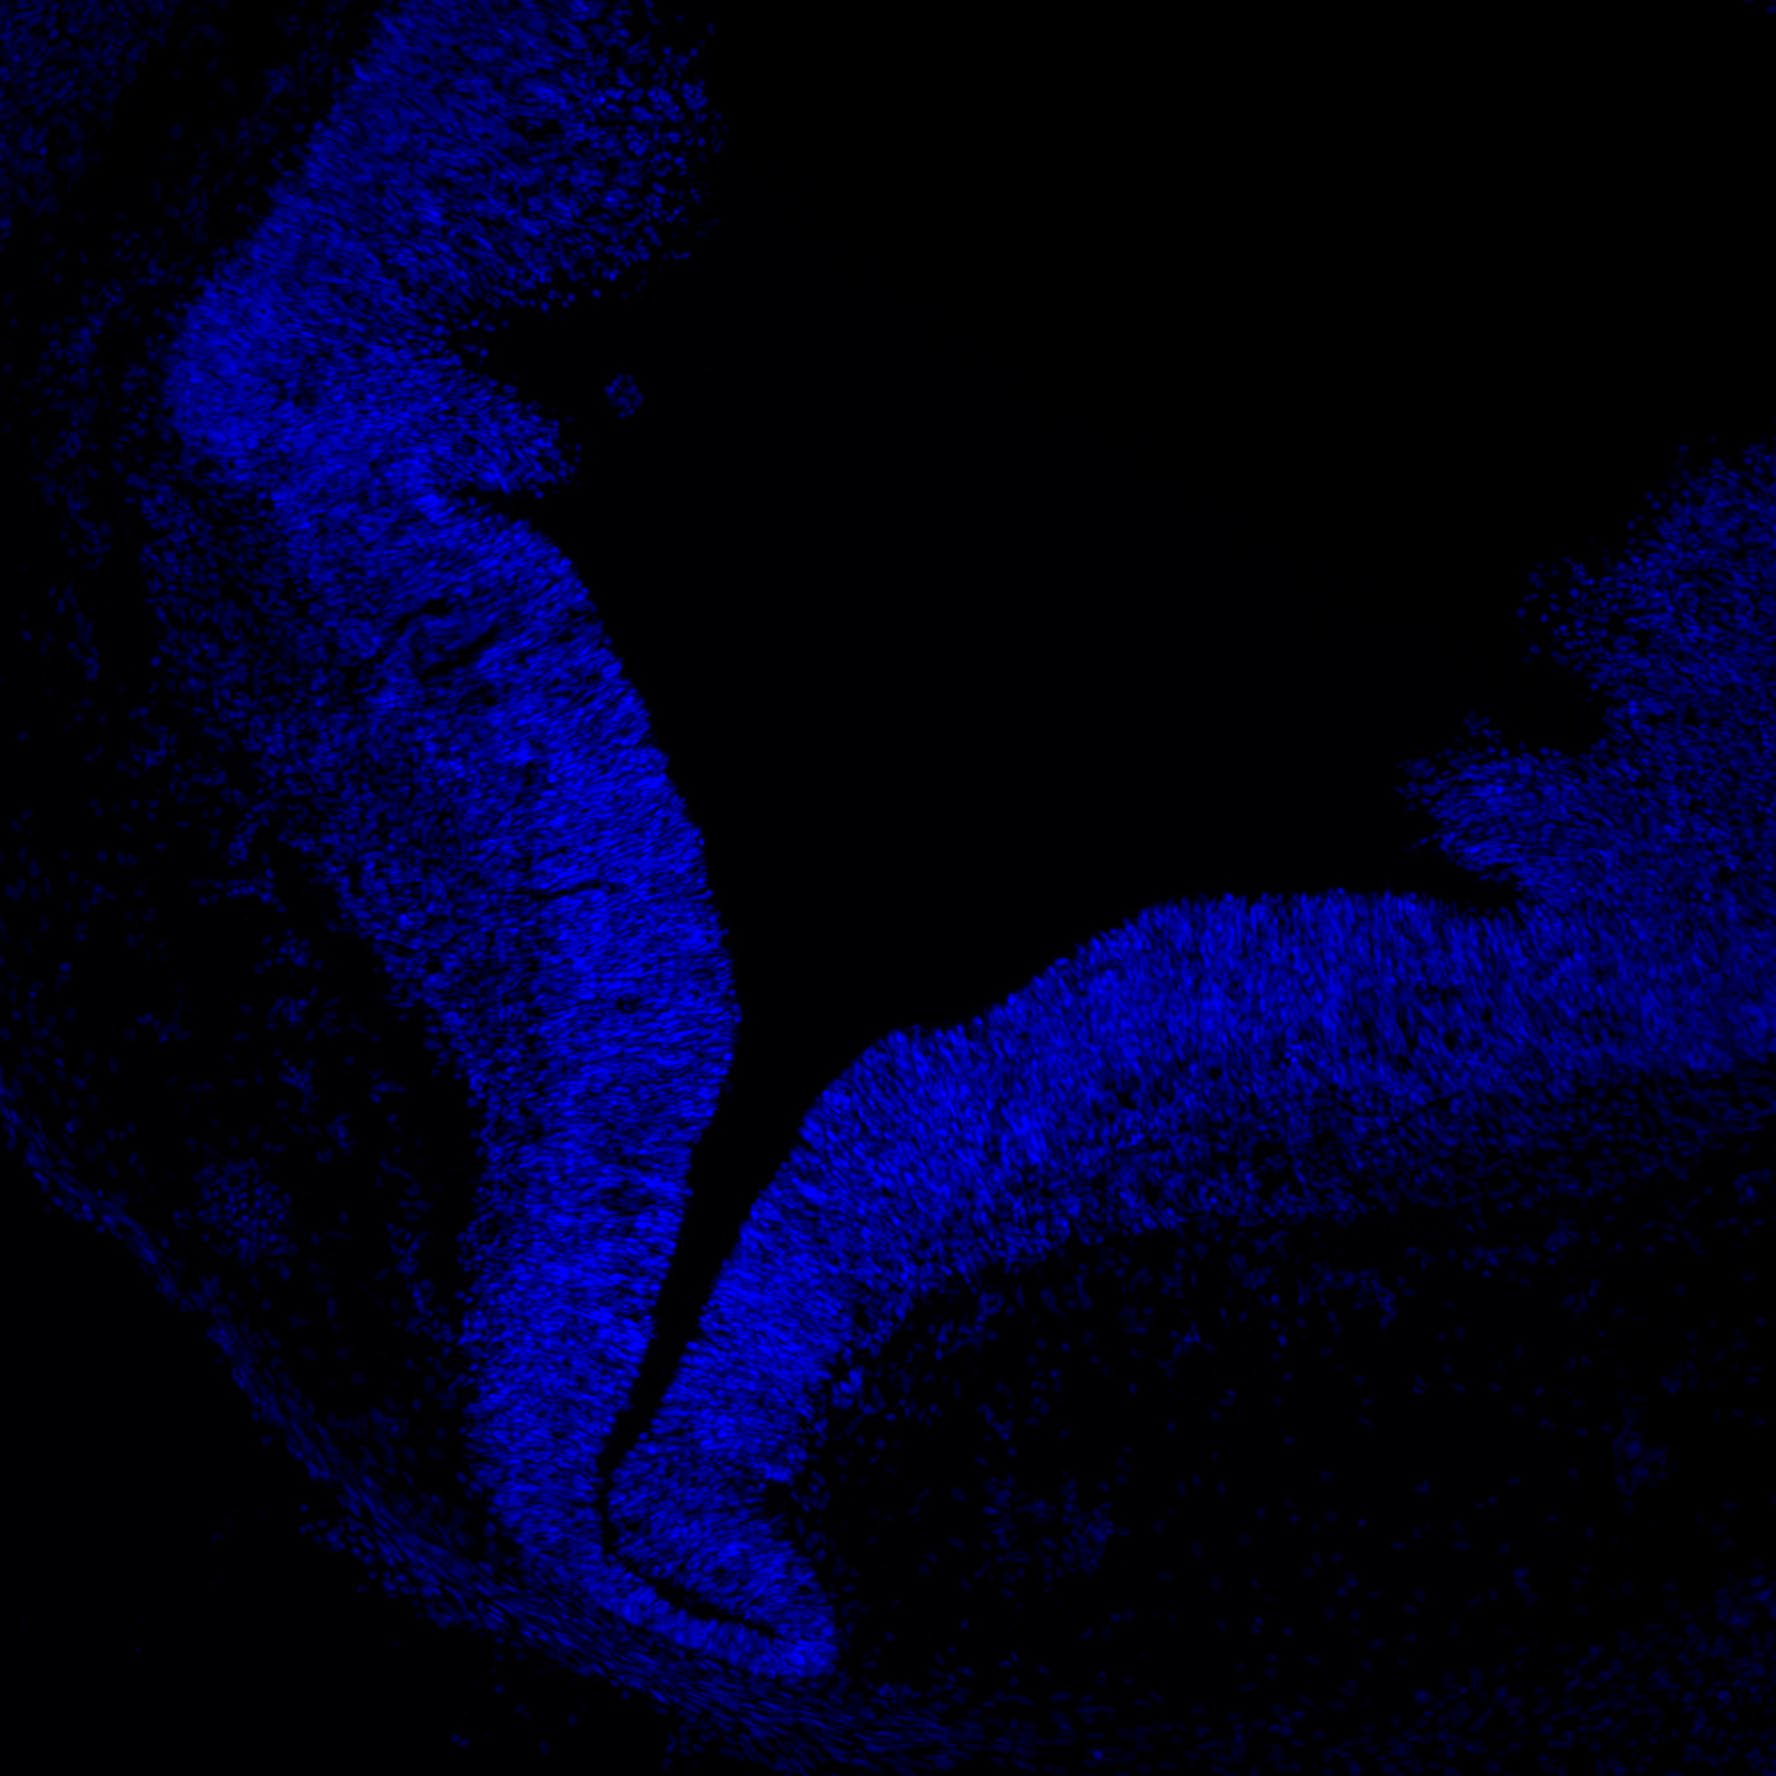

7PCW

DAPI

7PCW human midbrain